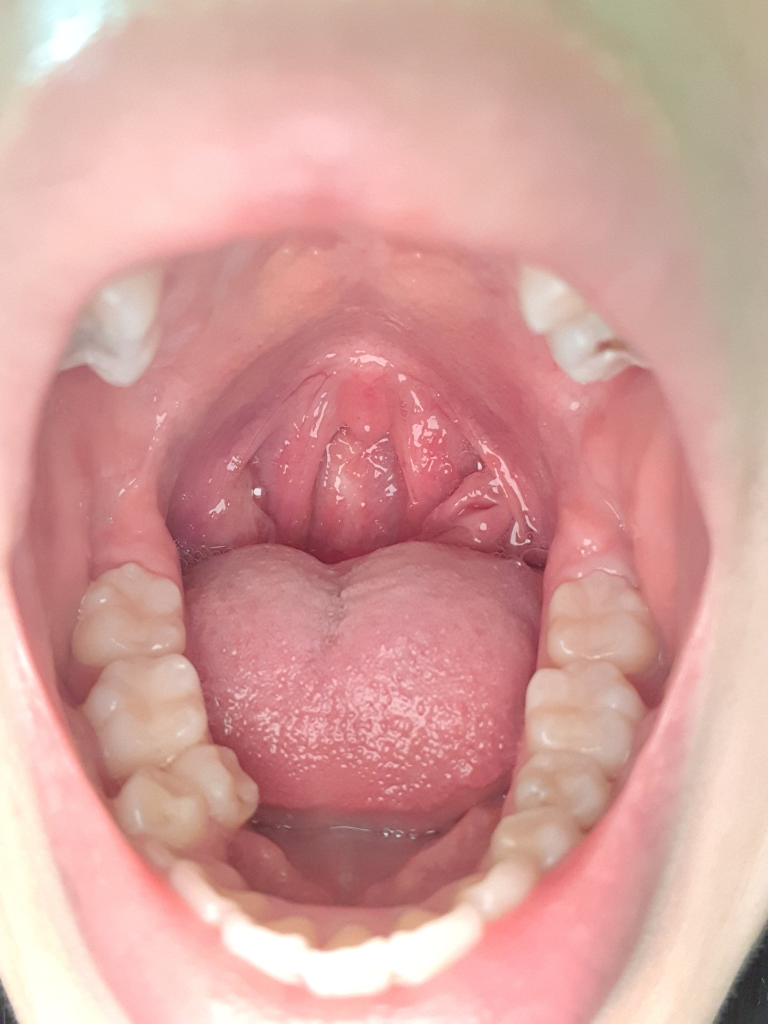

오른쪽 부분이 너무너무 아픕니다 그냥 있어도 아프고 침 삼켜도 아픕니다 사진 첨부해도 도움이 될지는 모르겠네요... 제발 아무나 도와주세요....

• 1번 째 사진

올리신 사진의 소견에는 특별히 이상 소견이 크게 의심스럽지 않아 보이나 인후통 증상이 지속된다면 안쪽에 염증이 있을 가능성을 고려하여서 이비인후과적으로 진료 및 검사를 받아보는 것이 도움이 될 수 있겠습니다.

편도염 소견이 관찰됩니다.